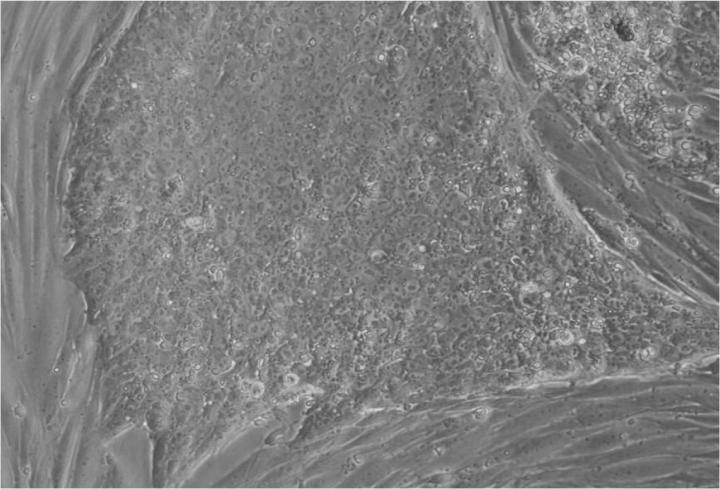

人类胚胎干细胞 (ESC) 是从囊胚(一种非常早期的人类胚胎)中发现的少量细胞产生的。从囊胚中取出的单个细胞生长成大量细胞以产生 ESC“系”。

大多数研究人员使用的ESC系是已经存在的干细胞系。大多数新的胚胎干细胞系都是由生育治疗中备用的囊胚制成的。

胚胎干细胞的自我复制能力允许从干细胞系中培养出大量细胞,并与全球实验室共享多年,从而最大限度地减少了从囊胚制造新胚胎干细胞的需求。

Jenny Nichols 拍摄的人类囊胚和人类胚胎干细胞图像。爱丁堡大学 MRC 再生医学中心向 SCNT 和多莉羊注射细胞核。